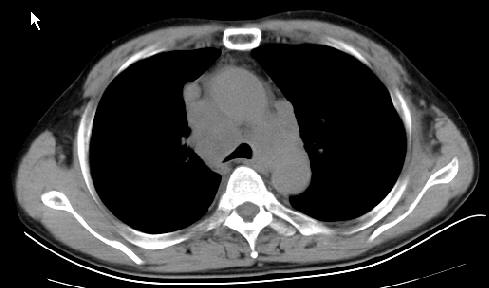

以下是引用草之原在2009-5-2 19:29:00的发言:[br]1.考虑右侧中心型肺ca纵膈淋巴结转移,双侧胸腔积液及右侧叶间裂积液,心包积液。[br]2.两肺上叶病灶,纵膈窗显示部分病灶硬化,考虑:结核。[br][br] [br]

以下是引用ct诊断高手在2009-5-2 19:08:00的发言:[br]我考虑右侧中央型肺癌 伴右肺节段性不张,两肺及纵隔淋巴结转移,右侧胸腔积液。

以下是引用zjzjr在2009-5-2 20:16:00的发言:[br]肺结核,转移瘤.纵隔淋巴结转移或淋巴瘤,右侧包裹性积液、斜裂积液。心包积液。